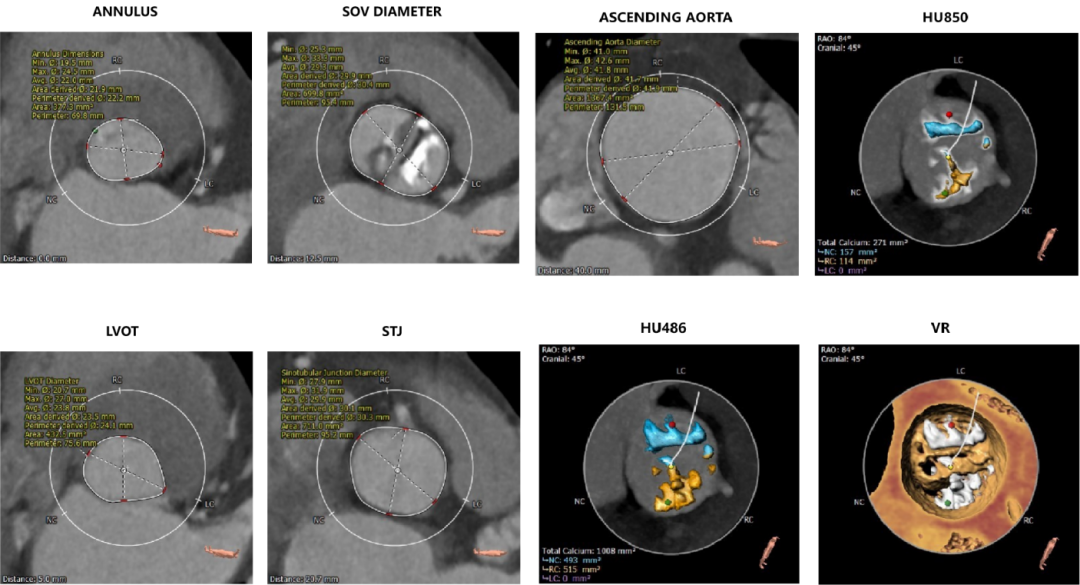

患者为70岁老年女性,主因“心悸30余年”入院。患者既往史明确,4年前于外院行开胸主动脉瓣膜置换术失败,改行保守治疗。1年来心悸加剧,外院诊断为“主动脉瓣重度狭窄”,遂自行前来上海就诊。行相关辅助检查后,超声提示“二叶主动脉瓣畸形、主动脉瓣狭窄(重度)、升主动脉增宽、二尖瓣反流(中度)。左室舒张末内径48mm;左房内径38mm;室间隔厚度10mm;主动脉瓣峰值压差91mmHg、平均压差58mmHg;LVEF 67%”。

主动脉根部评估:

左冠开口高度15.0mm,右冠开口高度15.0mm,双侧冠脉预估术后灌注良好;左室腔较小,心室壁可见明显增厚。